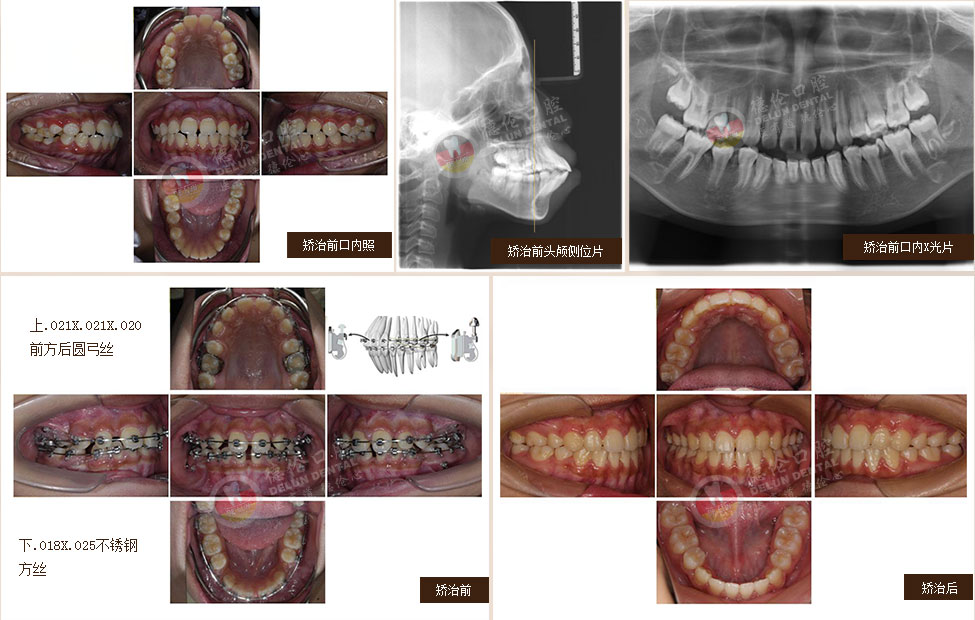

過去第一磨牙很早齲壞或缺失的患者只能拔除齲牙進行缺牙修復,若同時第三磨牙因阻生反復引起牙齒發炎疼痛,那么還要面臨拔除智齒恐懼??娫洪L通過多年臨床研究最終發明一種通過豎立智齒來代替齲壞或缺失的第一磨牙的方法,該技術刊登在2006全球權威口腔正畸學術雜志上,也稱為:“繆”院長的“妙技術”。

針對人群:下頜第一磨牙齲壞或缺失且下頜第三磨牙阻生。

備注:第一磨牙即六齡齒,人長出的第一顆恒牙。第三磨牙即智慧齒,最晚長出的恒牙。